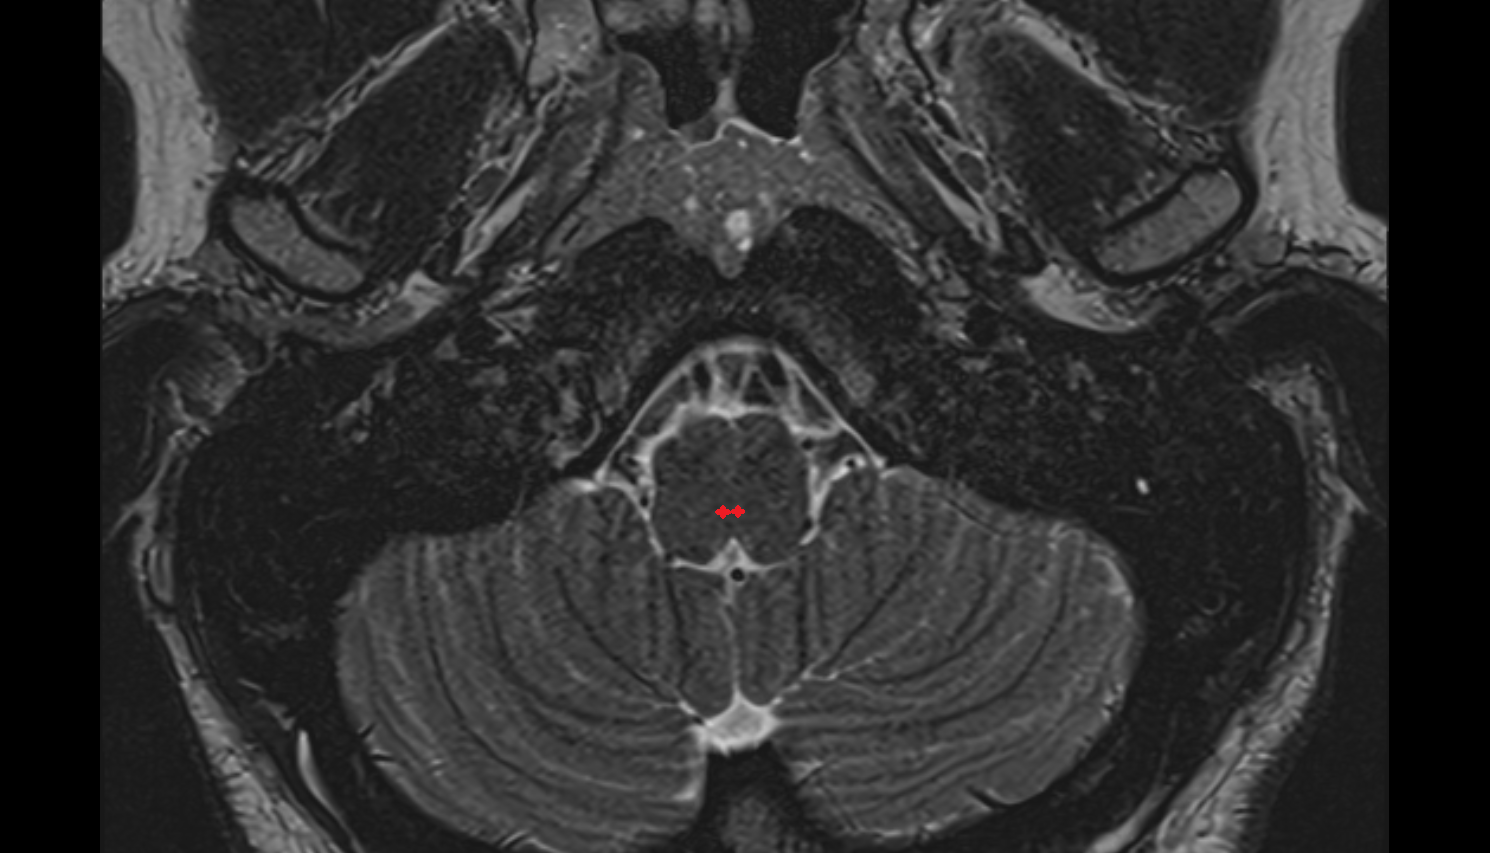

- Cornu ammonis

- Cornu Ammonis 1 (CA1)

- Cornu ammonis 2 (CA2)

- Cornu ammonis 3 (CA3)

- Cornu ammonis 4 (CA4)

- Dentate gyrus